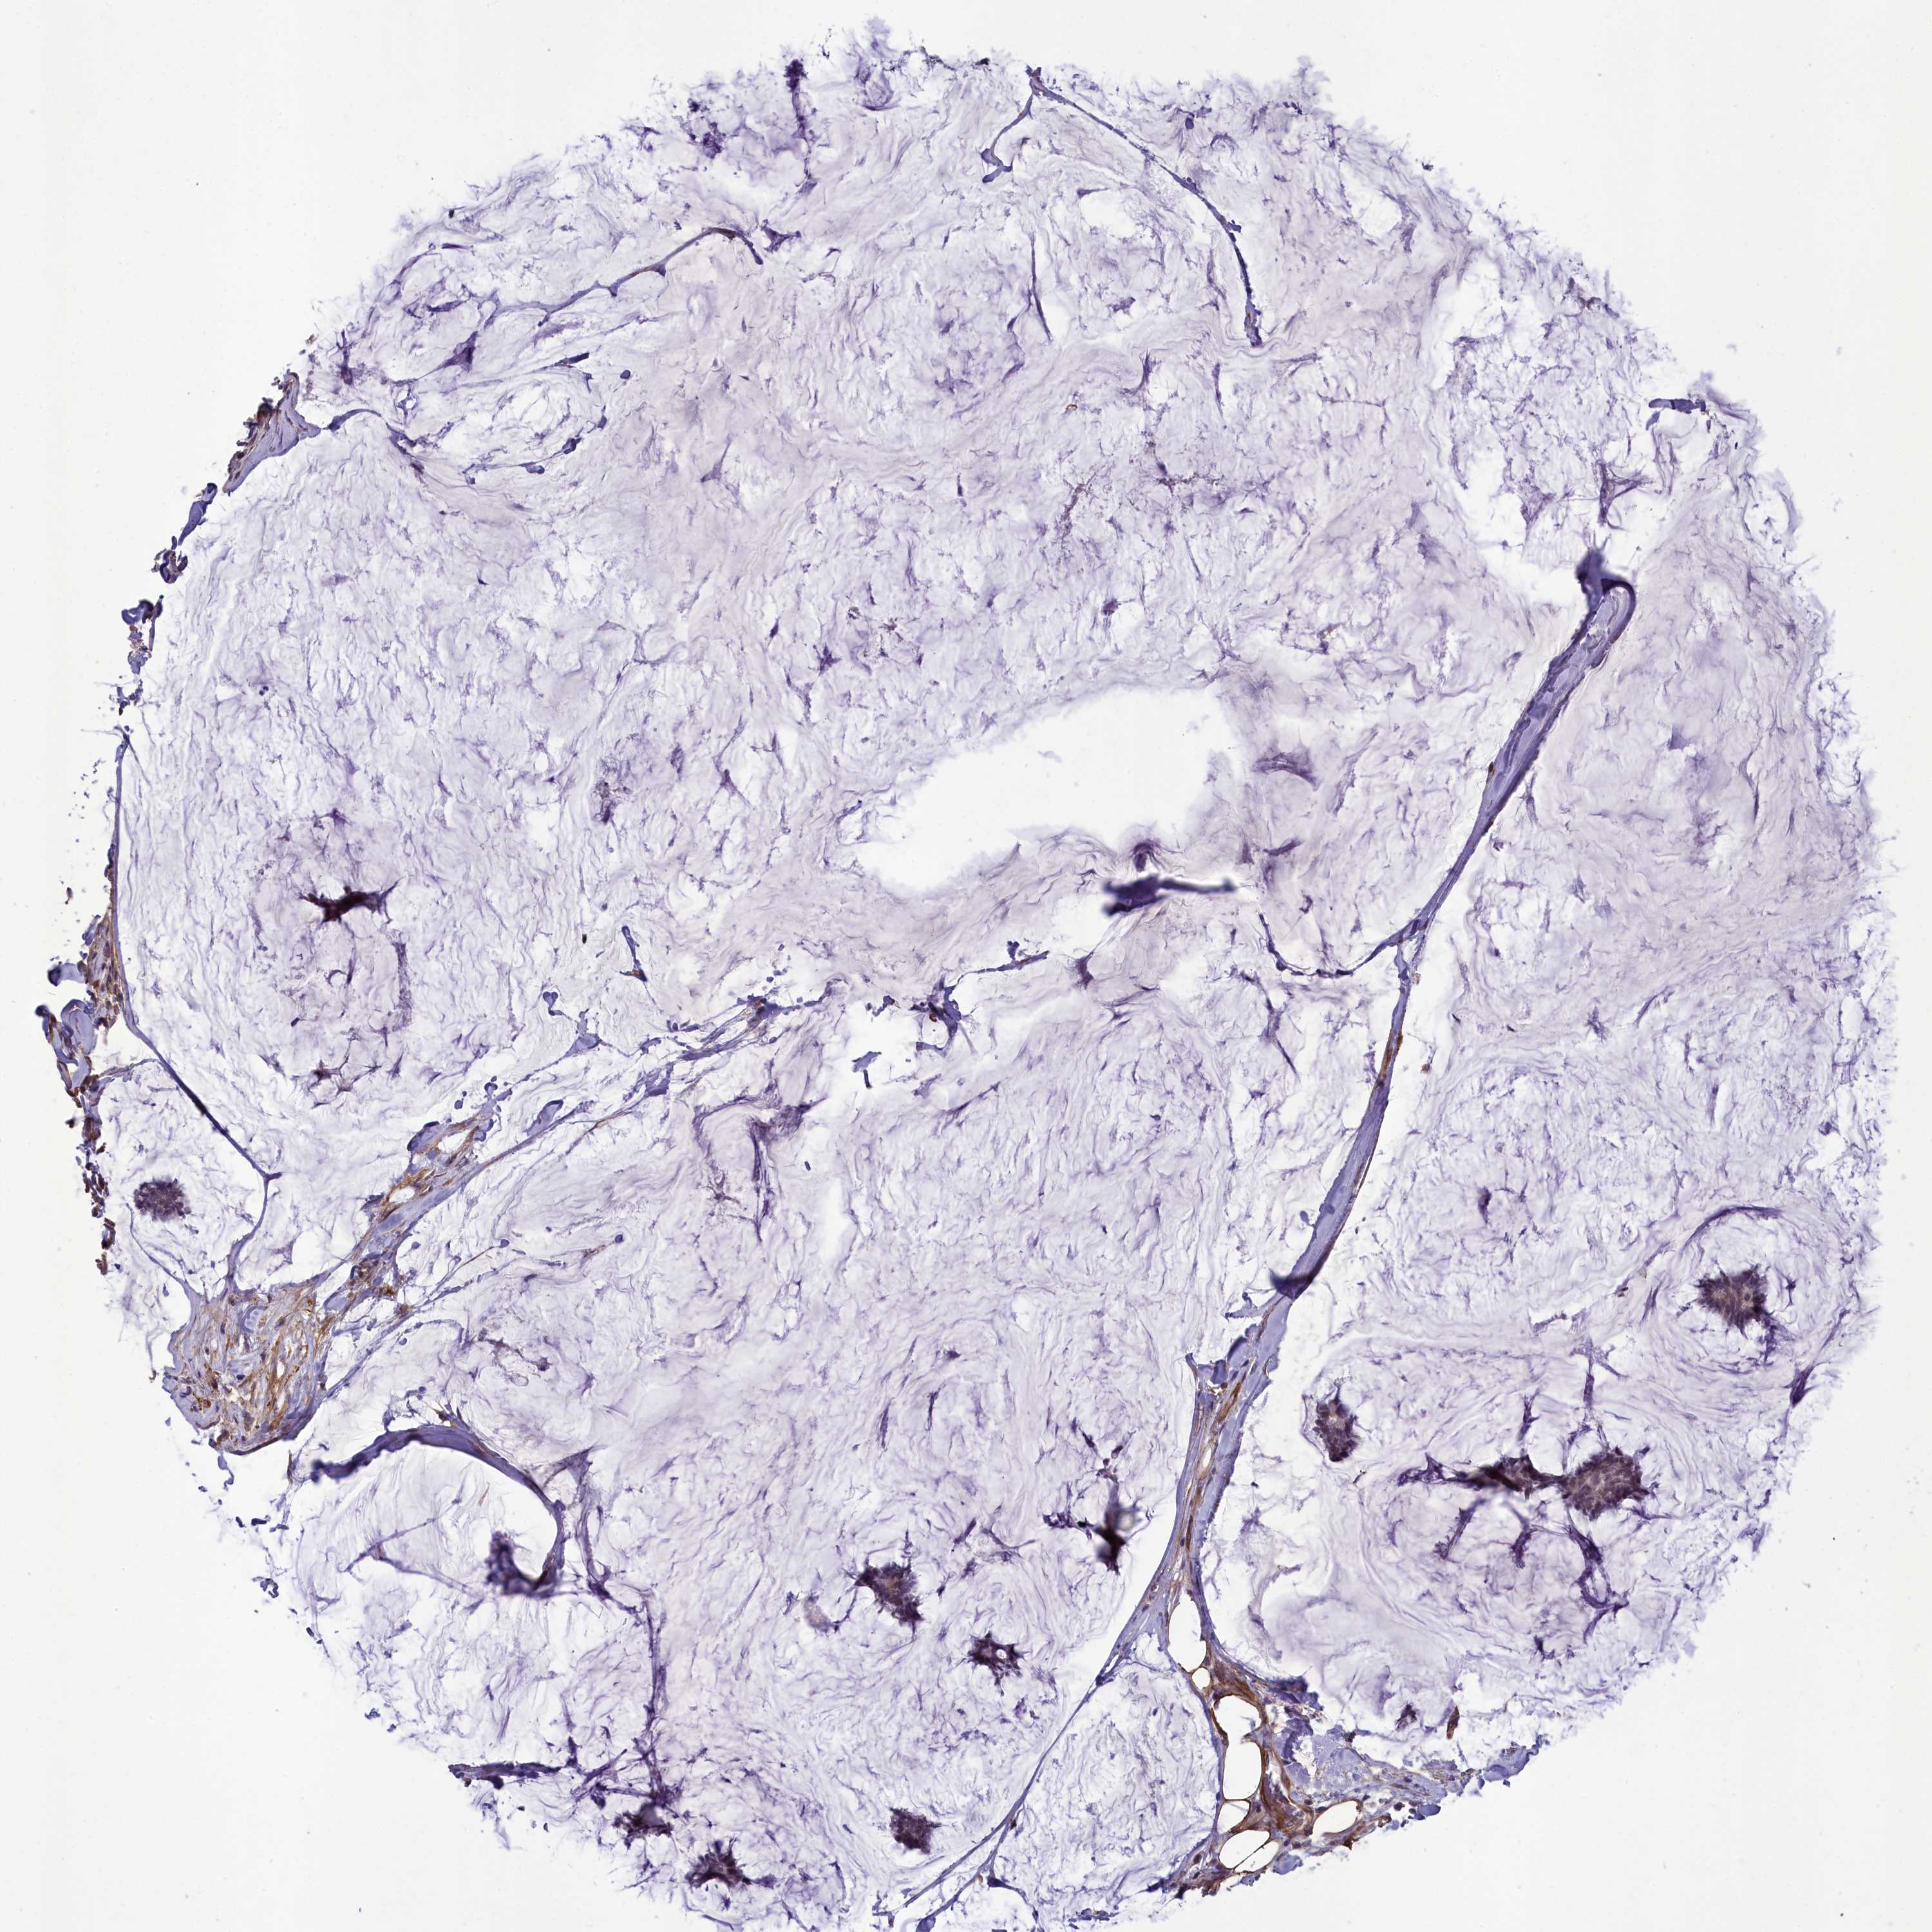

CANCER BREAST CANCER Show tissue menu

BRCA TCGA BRCA VALIDATION PROTEIN EXPRESSION